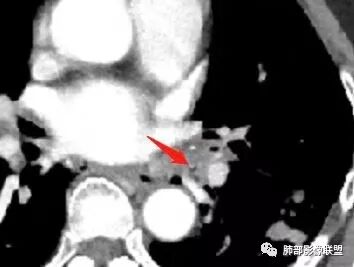

这三幅图是连续的,我们看到支气管中间这一幅狭窄了

大——小——大,狭窄后扩张

从这幅图看好像与周围病灶分界不清,支气管腔狭窄后扩张,支持炎性